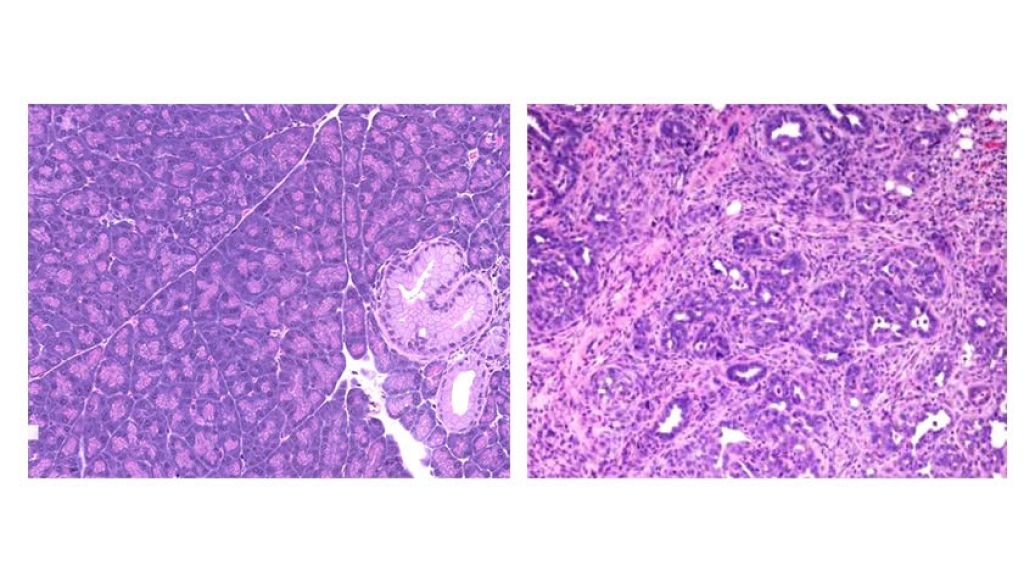

Microscopic pictures of pancreatic tissue in mice. The image on left shows tissue with precancerous lesions fed on a standard diet; the right shows the same tissue fed with a standard diet plus synthetic PPARδ added. Credit: Imad Shureiqi

Pancreatic ductal adenocarcinoma is a highly lethal form of cancer with rising occurrence, and strategies to prevent and treat the disease are urgently needed. Most cases of pancreatic cancer arise from pre-cancerous lesions called pancreatic intraepithelial neoplasia; about 55-80% of adults over 40 are estimated to have these low grade pre-cancerous silent pancreatic lesions. A study published in Nature Communications, led by Imad Shureiqi, M.D., shows that, pre-cancerous pancreatic lesions in mice, similar to those found in humans, contain higher levels of the transcriptional receptor peroxisome proliferator activated receptor-delta (PPARδ).

PPARδ regulates the expression of a wide spectrum of key genes that influences biological processes like lipid metabolism and cancer formation. Activation of PPARδ dramatically accelerates the progression of pre-cancerous lesions into pancreatic cancer. Shureiqi previously worked at MD Anderson Cancer Center at the University of Texas where he conducted much of this study, specifically in partnership with Xiangsheng Zuo, M.D., Ph.D., before moving his research to the cancer center in 2020.